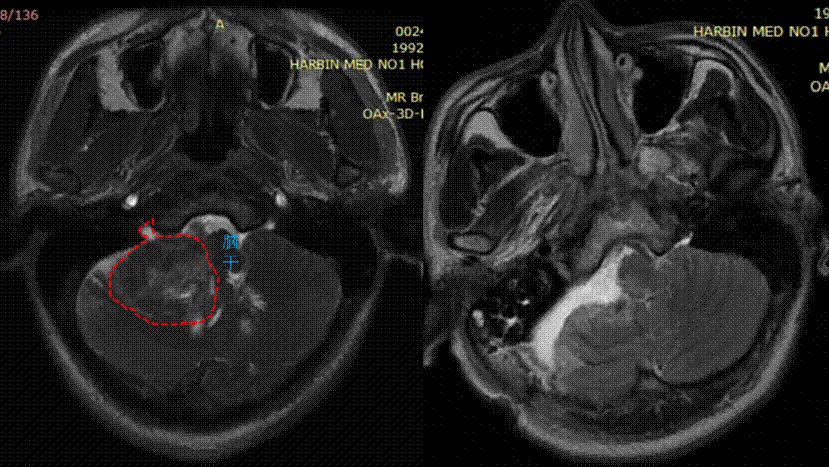

王女士半月前因头晕查体时发现听神经瘤,右侧听力虽有明显下降,但尚存有部分听力。患者慕名找到ac米兰官网中文网站一院高成教授救治,在得知术后可能发生的听力完全丧失和面瘫等潜在并发症后,患者十分紧张和焦虑。

高成教授与患者充分沟通和心理疏导,减少患者焦虑的同时,与电生理监测团队一起制定了周密和详细的手术预案。术中高成教授听神经瘤MDT团队凭借精湛的手术技巧,通过仔细分离覆盖在听神经瘤表面的“膜性结构”和肿瘤粘连紧密的面神经和听神经,在电生理监测的辅助下全切肿瘤的同时,顺利保住了患者的面神经和听神经。术后王女士无任何面瘫,听力较术前明显好转,并顺利出院。

高成教授指出,听神经瘤一旦诊断,一般首选手术治疗。由于听神经瘤生长位置深在,周边脑神经密集,内侧紧邻脑干,操作空间狭小,因此手术难度较高,手术时间相对较长,对术者的手术操作精细度和耐力,以及手术器械都要求极高。尤其是术中面神经和听神经的保护非常重要,一旦面神经受损患者术后会发生口角歪斜,眼睑闭合不全等面瘫症状,严重影响患者的生活质量和精神状态。